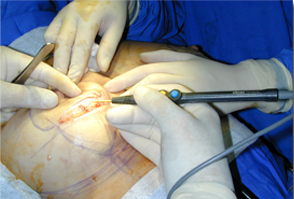

對軟組織切口的比較